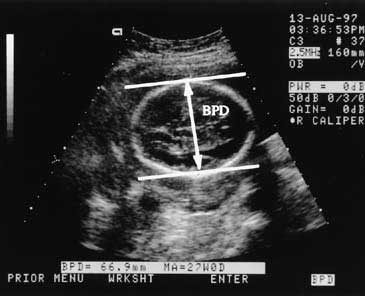

اندازه نرمال سر جنین (BPD) در سونوگرافی : اهمیت بررسی ها و راهکارها

اندازه گیری دقیق بی پاریتال دایامتر (BPD) یا قطر دوطرفه سر جنین یکی از شاخص های مهم در سونوگرافی بارداری است که به ارزیابی رشد و سلامت جنین کمک می کند. این شاخص برای تعیین سن بارداری تشخیص ناهنجاری های احتمالی و ارزیابی رشد جنین به طور گسترده استفاده می شود.

bpd در سونوگرافی جنین چیست؟ بی پاریتال دایامتر (BPD) فاصله بین دو قسمت برجسته از استخوان های جمجمه جنین است که در نمای عرضی سر اندازه گیری می شود. این شاخص معمولاً از هفته ۱۳ بارداری به بعد قابل اندازه گیری است و نقش مهمی در :

محدوده های نرمال BPD در هفته های بارداری

در جدول زیر محدوده های نرمال قطر دوطرفه سر جنین (BPD) بر اساس سن بارداری ارائه شده است :